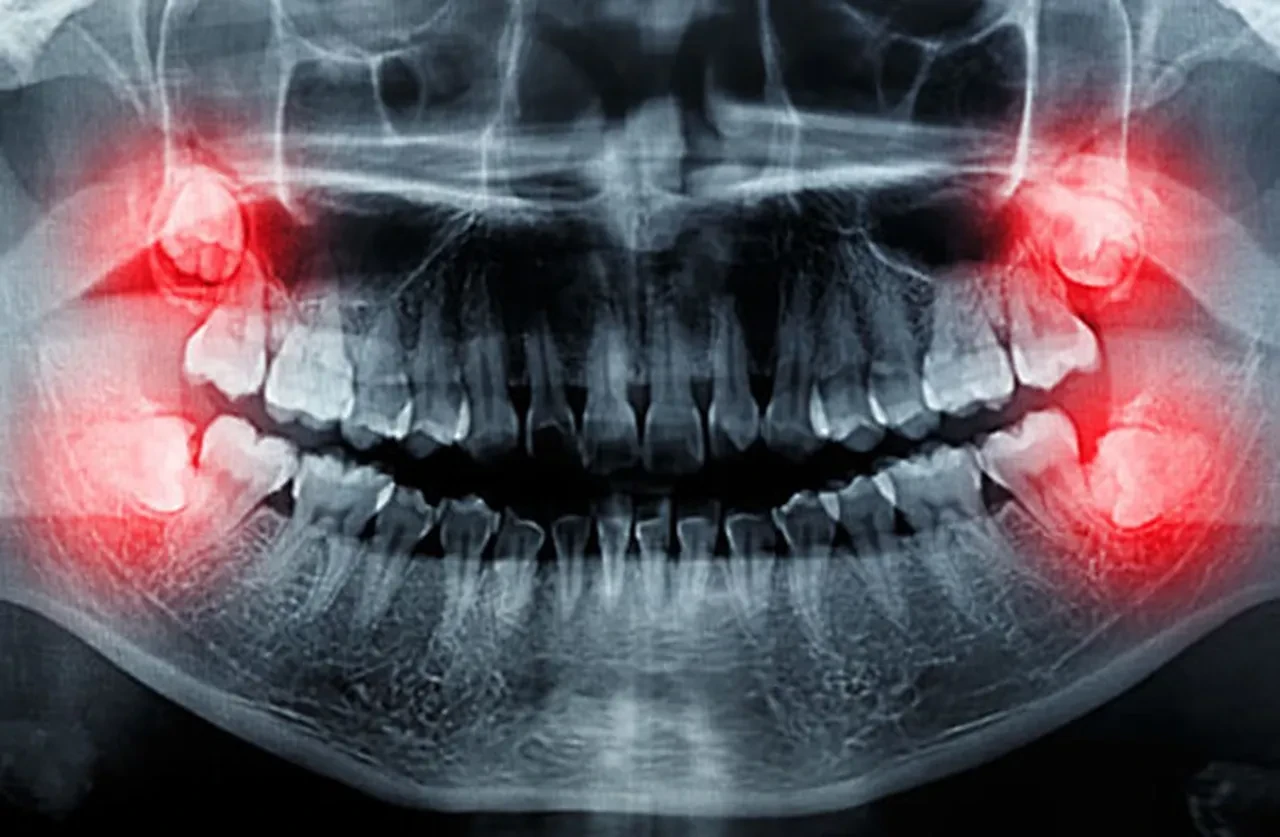

Uzun süredir yalnızca cerrahi operasyonla çekilip atılan yirmi yaş dişlerinin, aslında sağlık alanında büyük bir potansiyel taşıdığı anlaşıldı.

Ancak ABD ve Avrupa’da yüzde 80’i aşan oranlarda önleyici çekimlerle ortadan kaldırılan bu dişler, artık bir çöp değil, yüksek tıbbi değer taşıyan bir hazine olarak görülüyor.